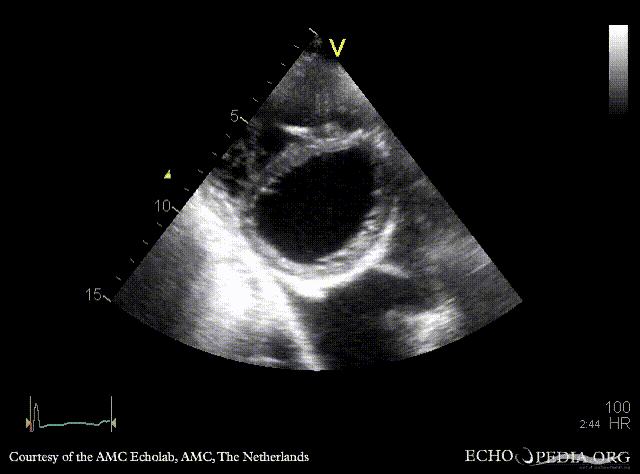

E00452.gif E00453.gif

PSAX: flattening of IAS, enlarged right ventricle PSAX: prolaps of PMVL